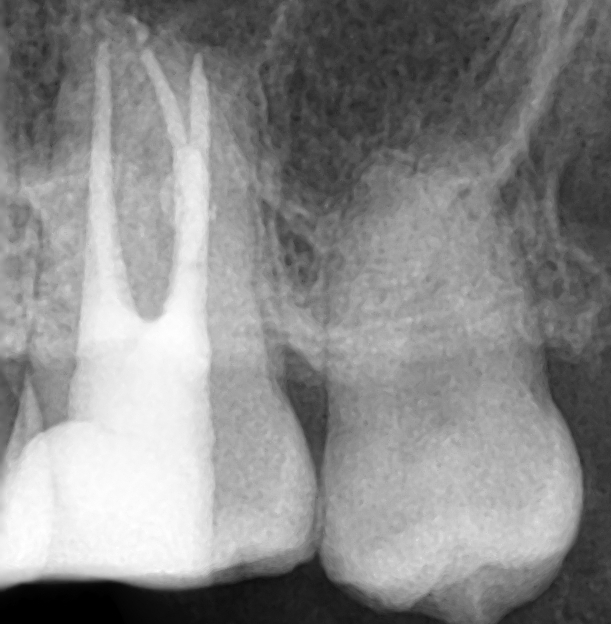

신경치료가 끝난 후 엑스레이 입니다. 하얗게 충전물질들이 보입니다.